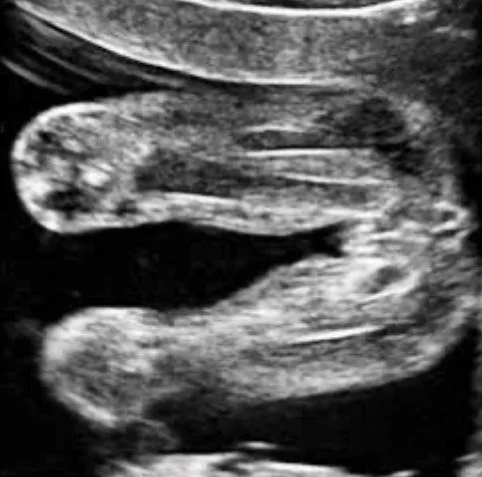

For more accuracy, I definitely recommend booking an early gender reveal ultrasound from 14 weeks onward. Baby’s nub has developed sufficiently enough then to have a clearer evaluation. We can be more sure of whether you’re having a boy or girl after 14 weeks.